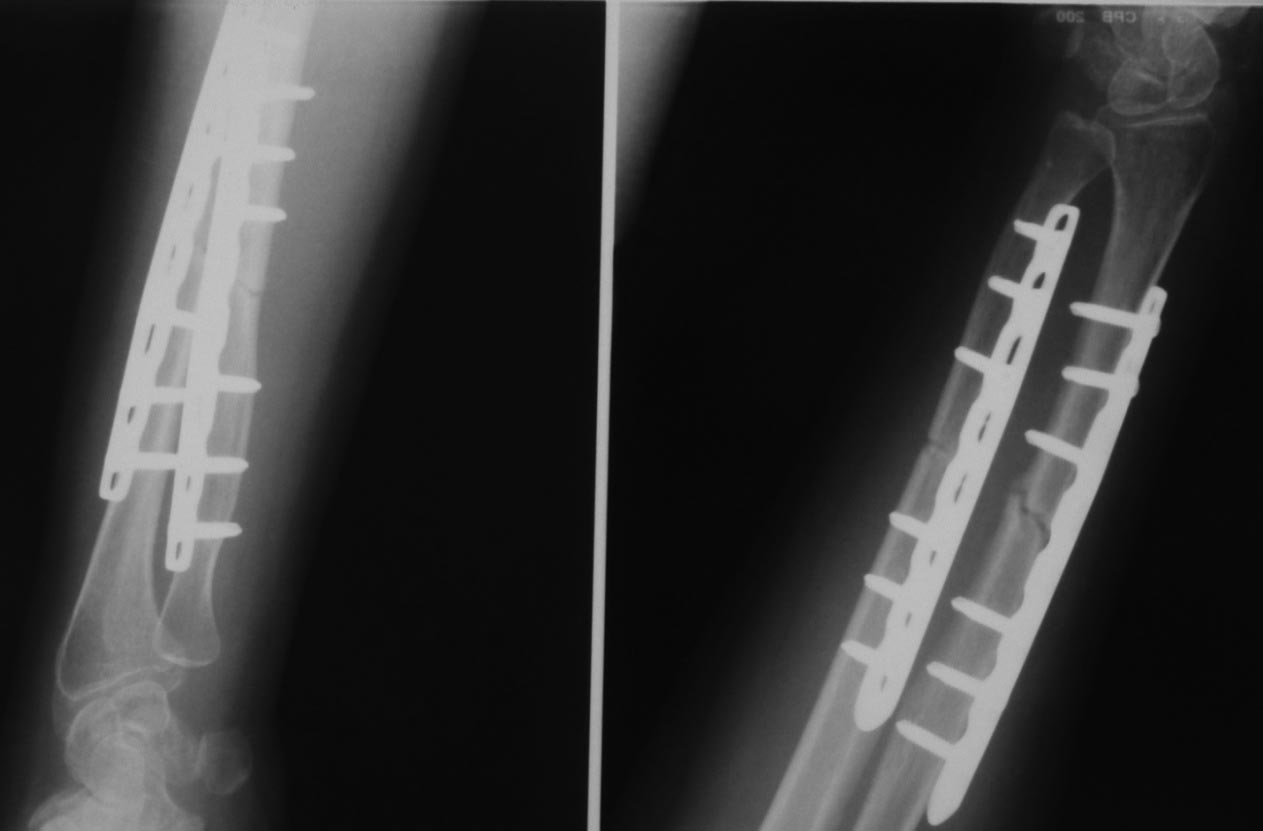

Уважаемые коллеги.Пациентка 45 лет прооперирована по поводу перелома костей предплечья

26.01.12. Послеоперационый период гладкий, функция предплечья восстановилась. 12.05.12

упала повторно (обморок).

Диагностирован перелом головки локтевой кости. На мой взгляд, имеется и перелом по ходу

дистального винта лучевой кости (появилось разрежение вокруг винта, которого не было на

рентгенограммах через 1.5 мес. после операции). Хотя, локальной болезненности в этом месте

нет. Болит в проекции кистевого сустава. Вопрос: показано ли удаление этого винта? Не будет

ли он препятствовать консолидации? Заранее спасибо за ответы.